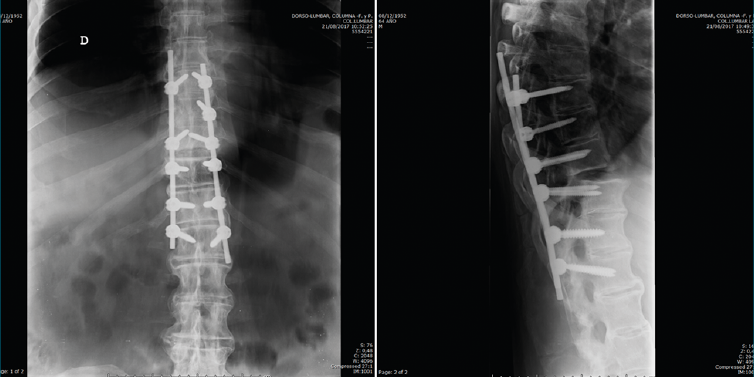

Figura 6. Control postoperatorio.

Después de realizar un control radiológico postoperatorio (Figura 6), inició la deambulación con ortesis semirrígida dorsolumbar en el postoperatorio inmediato. Mantuvimos la ortesis durante 2 meses, iniciando la rehabilitación con una evolución clínica excelente.